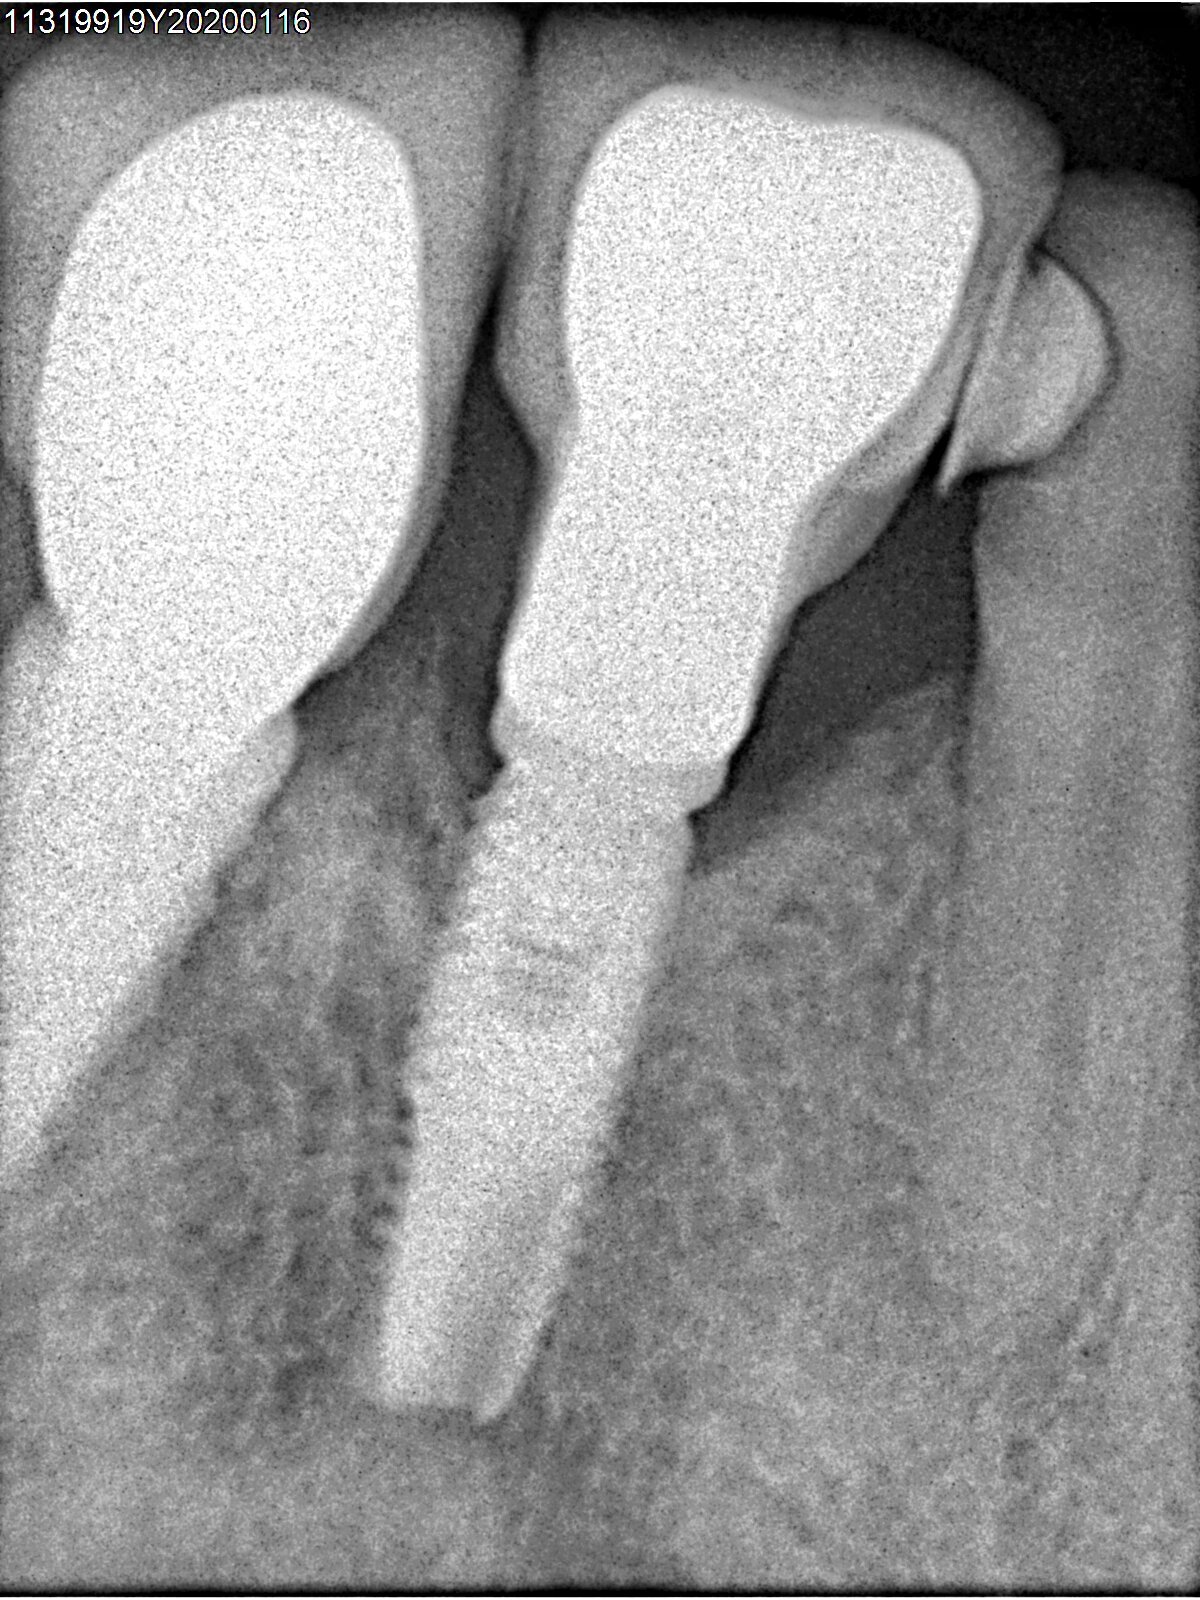

Que implante es el 36?

Buenas tardes compañeros. Acudo a vosotros para ver si me podéis ayudar. Sabríais decirme marca y modelo? Gracias!